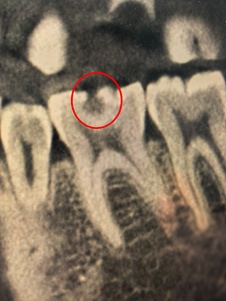

接近牙神经的龋洞

近日,杭州的李女士(化名)捂着半边脸来到杭州师范大学附属医院口腔医学中心,经检查,牙体牙髓专科负责人陈幸副主任医师发现她的牙齿已有深龋洞波及牙神经,必须做根管治疗。

无糖碳酸饮料里的酸,会直接酸蚀牙釉质导致“牙齿脱矿”,破坏力不输糖;果干黏稠、糖分高,特别容易粘在牙齿缝隙里,成了细菌滋生的温床。这些“隐形酸”与“隐形糖”悄然损害牙齿,待出现冷热刺激痛时,龋坏往往已深达牙齿内部。